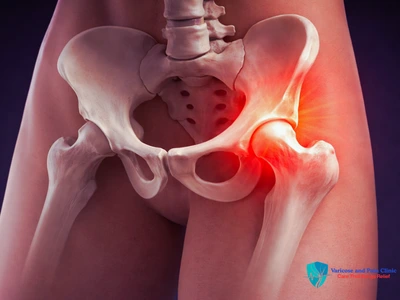

Hip Joint Pain Treatment